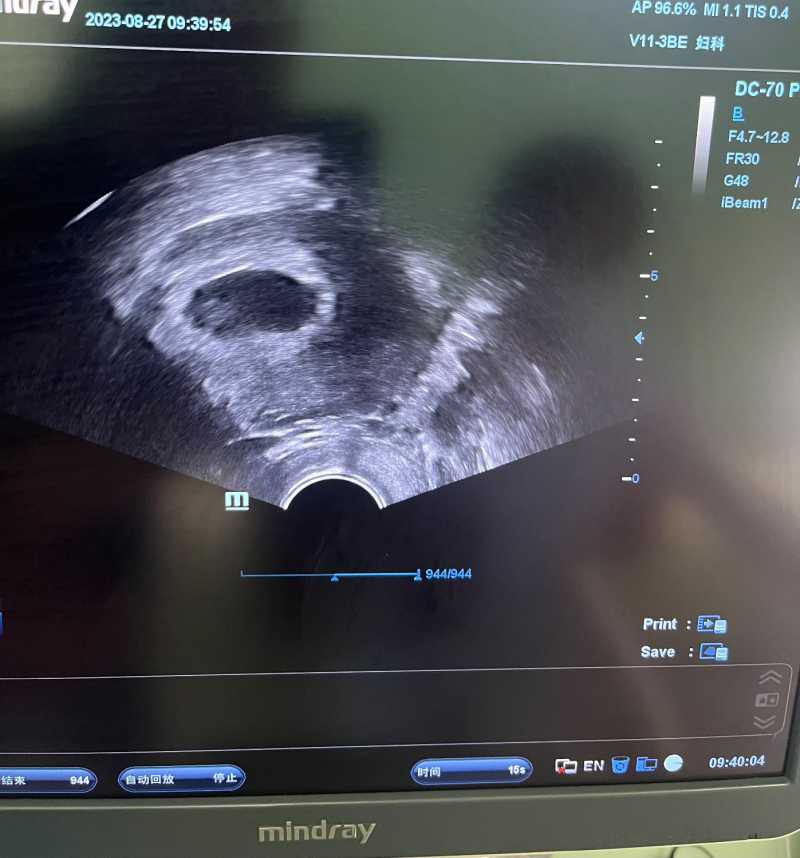

宝宝8周三天了,七周的时候去检查,胎心胎芽都有了,血管搏动也清晰可见,主任连续说了三遍:胎儿发育很好,心情无比开心,要我九周来院,转妇产科,约nt,停保胎药,由于是大龄,医院会全力保胎,一直有开保胎药,但我一直没有不舒服,所以吃一顿不吃一顿的。上上次检查,医生确认宫内,但是有点偏右边宫角,且孕囊6×9,积液17×9,比孕囊还大很多,医生问我着床期间是不是一直干重活,我说那段时间公公住院,的确是辛苦些,但也没多重,医生强调回家必须卧床休息,说胎盘长出来之前,宝宝是伸出小触手爬在子宫壁吸收营养,旁边长个比宝宝还大好多的积液,如果积液不消失甚至继续长大,就会把宝宝挤下来,很危险,而积液的形成是因为摩擦,所以要尽可能静养,偏右侧得左躺,回家后尽量按医生说的做了,两周后复查,积液减小了一半,孕囊长大了好多,位置也长回去了,一切都很好,我的宝宝真棒,从有积水的输卵管使劲游出来,这么厉害,心里有种被宝宝坚定选择,双向奔赴的感觉,暖暖的,软软的。